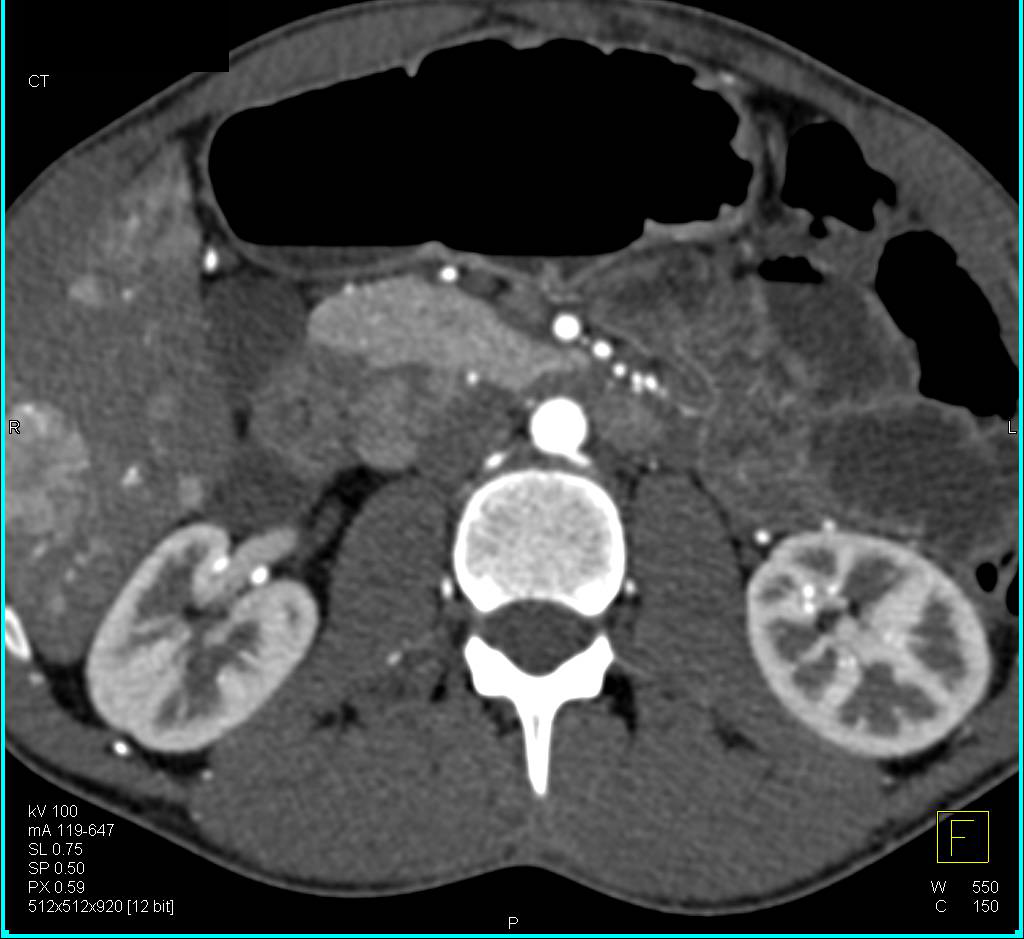

from www.ctisus.com

From ctisus.com

Primary hepatic neuroendocrine carcinoma. Computed tomography Neuroendocrine Cancer Liver Neuroendocrine liver metastases (nelm) are heterogeneous in clinical presentation and prognosis. Most patients fall into one of two groups. Primary tumor resection with resection of liver metastases is the treatment of choice for patients with nelms. However, although appendix is the most common location for. Neuroendocrine tumors have extremely been rare in liver. Some seek help for symptoms,. How are. Neuroendocrine Cancer Liver.